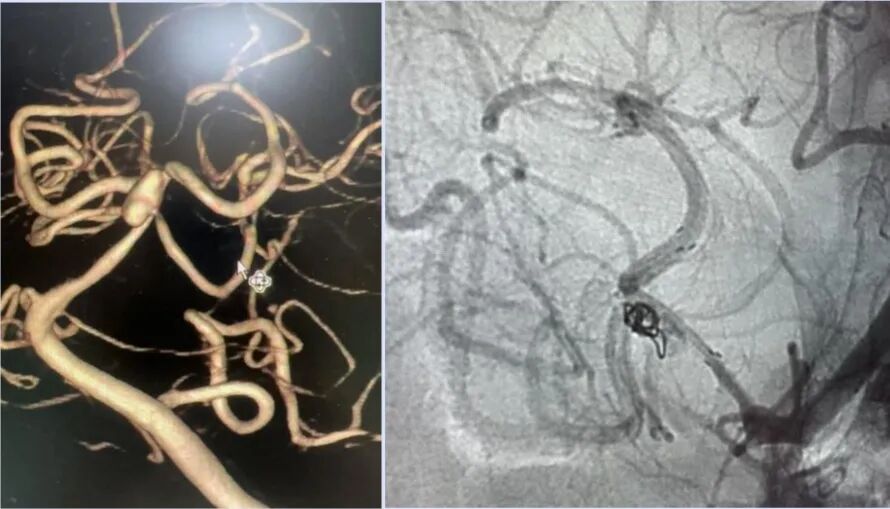

59歲男性,突發(fā)頭痛、嘔吐1小時,被診斷顱內(nèi)動脈瘤

以上患者發(fā)病后,被緊急送往惠州市第三人民醫(yī)院治療。經(jīng)過神經(jīng)醫(yī)學中心腦血管治療團隊的介入手術治療后,均得以恢復,目前在康復中。惠州三院神經(jīng)外科景英朝主任醫(yī)師介紹,在一年四季中,夏季并非卒中的高發(fā)季節(jié),然而,夏季的某些特定因素,卻可能成為誘發(fā)卒中的重要因素,群眾在日常生活中要注意預防,避免意外的發(fā)生!